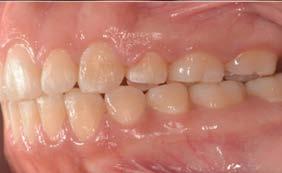

Caso clínico: paciente femenino de 19 años, patrón dolicofacial, perfil convexo, clase II esqueletal debido a una retrusión mandibular, mordida abierta anterior esqueletal, clase II molar, clase canina no establecida por mordida abierta, apiñamiento severo superior e inferior y deglución atípica.

Resultados: obtención de una clase canina I y clase molar II funcional, se corrigieron las sobremordidas horizontal y vertical, y se logró la coincidencia de líneas medias facial y dental. El manejo de la mordida abierta anterior se llevó a cabo por medio de la corrección del hábito de deglución atípica con la ayuda de spikes de resina, elásticos intermaxilares y arcos utility, y se obtuvieron buenos resultados estéticos, dentales y funcionales.